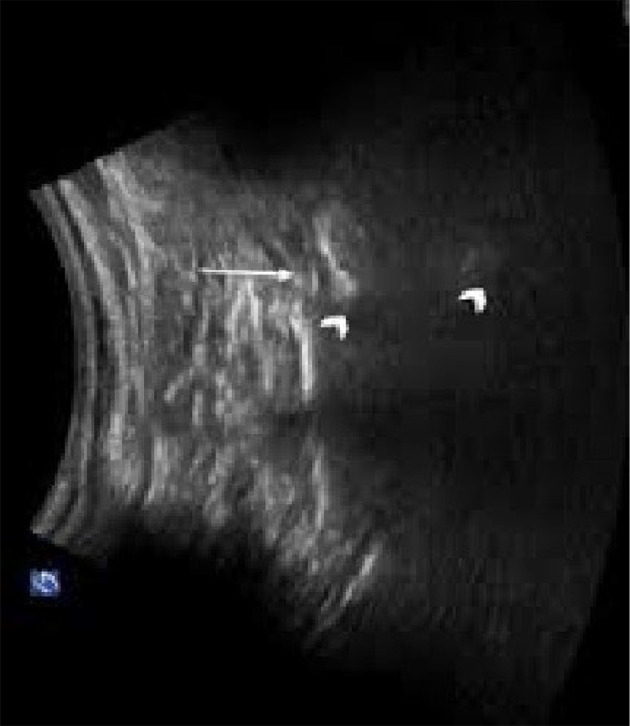

Methods: A randomized double-blinded clinical trial was conducted involving 52 PLSS patients who were randomly assigned to either the CESI group or the S1-TFESI group. The patients were positioned prone. A linear transducer with a curve at a low frequency (2 - 5 MHz) was used to visualize the area. An aseptically prepared puncture site was used to insert a 2- to 5-MHz curved ultrasound probe with an ultrasound gel to identify the articular processes of the lower lumbar vertebrae and the posterior sacral surface. The probe was then positioned longitudinally to the para-sacral area, about 2 cm lateral to the midline. The articular process represented the L5/S1 level at the farthest caudal side, and the S1 posterior sacral foramen was represented by the concavity at the posterior sacral surface that was somewhat caudal. The probe was angled caudally to provide enough room for the needle to enter the S1 foramen. The injection site for the needle tip was the S1 foramen. A combination of triamcinolone (40 mg, 1 mL), normal saline (2 mL), and ropivacaine (0.2%) was administered. For TFS1 ESI, 5 mL of the combination was used. For CESI, the sacral hiatus was palpated in the prone position, and a linear high-frequency transducer was placed transversely to obtain a transverse view of the sacral hiatus. A combination of triamcinolone 40 mg and ropivacaine (0.2%) totaling 10 mL was employed. The Numerical Rating Scale (NRS) and Oswestry Disability Index (ODI) were used to assess patients' preoperative and postoperative conditions, and adverse events were recorded. Follow-up was conducted one week and one month after the procedures.